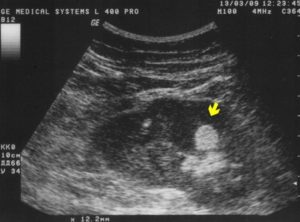

Врач на экране определяет включение по светлому, почти белому пятну, и сразу обращает внимание, отбрасывает ли обнаруженное включение акустическую тень, то есть сгусток непрошедших сквозь него ультразвуковых волн.

Как выглядит гиперэхогенное образование на УЗИ Если в полости почки, а чаще обеих, обнаруживаются уплотнения большого объема (0,5-1,5 см3), отбрасывающие акустическую тень, они указывают на камни внутри почки.